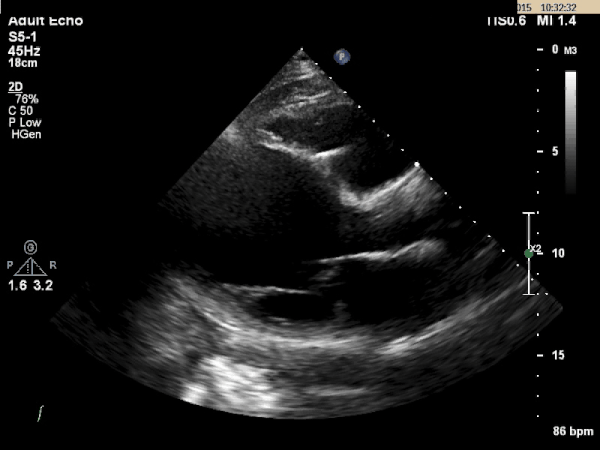

Echocardiogram